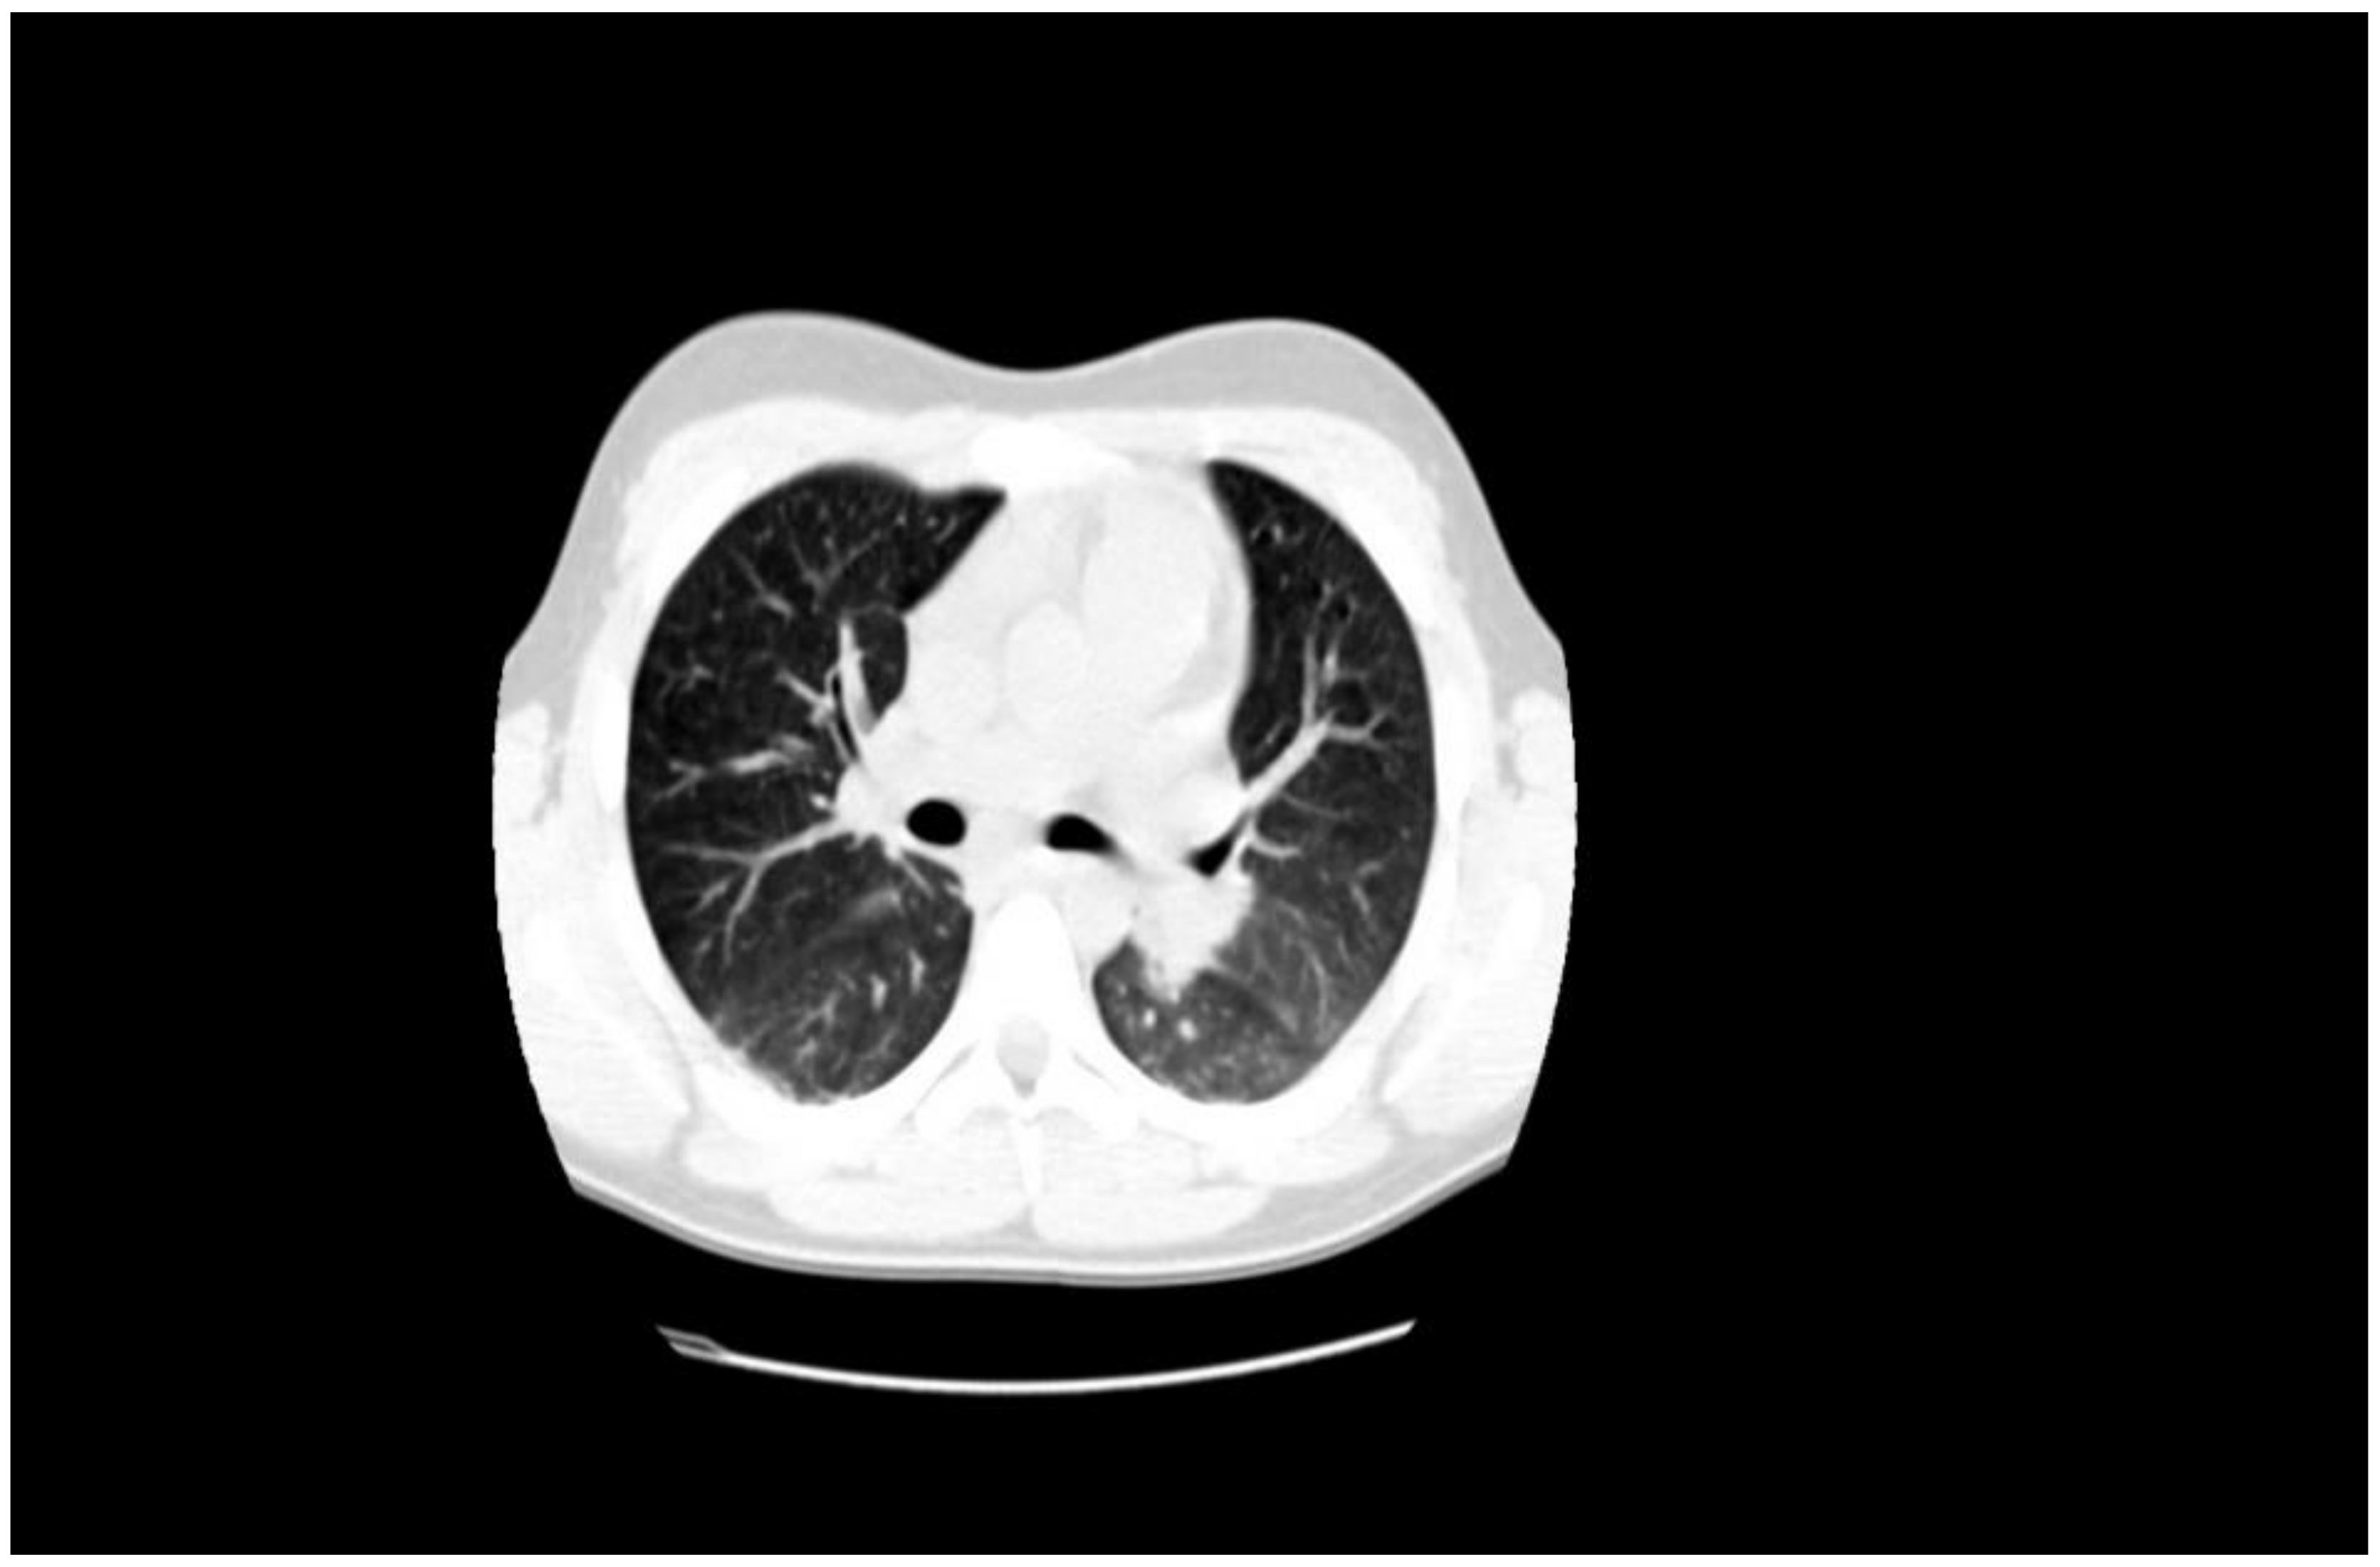

1.1. Case Presentation #1

1.2. Case Presentation #2